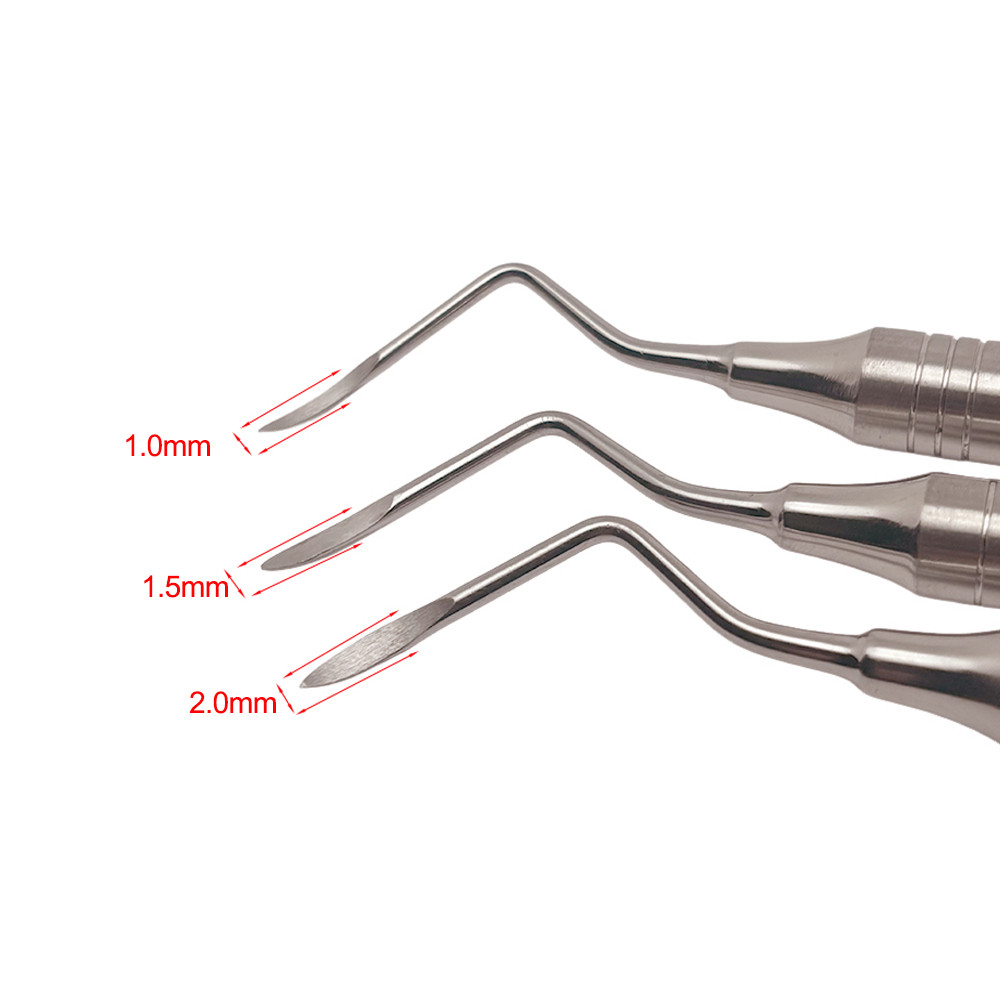

3 Variations Available

Dental Minimally Invasive Extraction Tool Root Tip Pick Elevator with Sharp Tip for Dental Implant Tooth Extraction Surgical